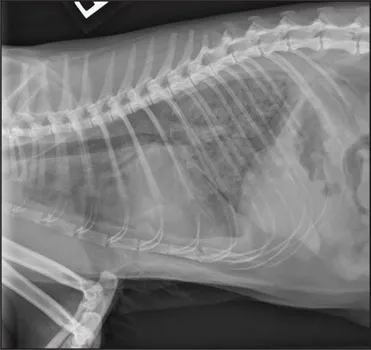

CASE 1.1 A 7-year-old neutered male Labrador Retriever who was hit by a car. You obtain these thoracic radiographs: Figs. 1.1a, b, left and right lateral projections, respectively; Figs. 1.1c, d, ventrodorsal and dorsoventral projections, respectively.

1.1a

1.1b

1.1c

1.1d